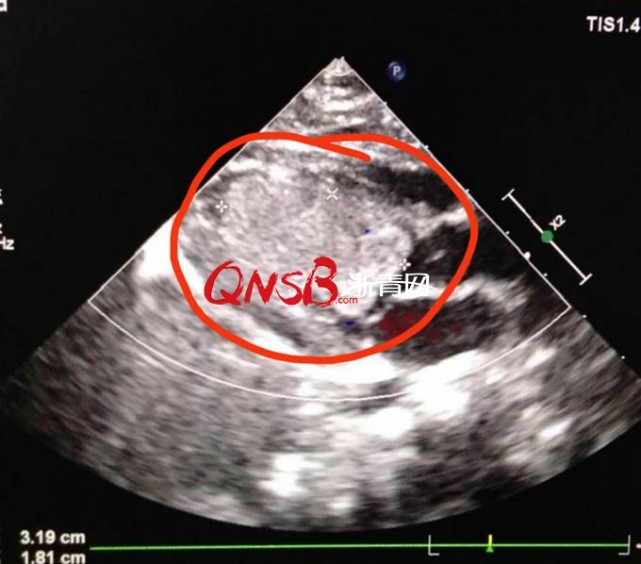

3个月大宝宝吃完奶心脏骤停 原来小心脏里长了

天 问题描述:我的宝宝心脏有杂音,心内结构显示欠清,初步提示:左房稍大请问一下心脏不好会引起婴儿不吃奶吗?

你好,根据你的宝宝症状。考虑是急性的心肺发育不全引起的。需要注意这是 先天性心脏病 中最轻的一种病症.